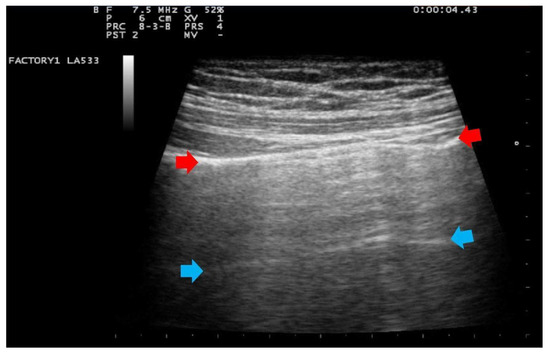

- Score 1:

- Score 1: at least three B-lines or confluent B-lines which occupy ≤ 50% of the screen without irregularities of pleural line. (Figure 2) Score 1p: B-lines with a clearly irregular pleural line.